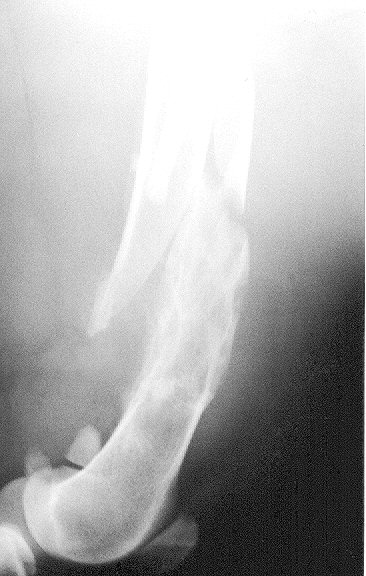

Proximal Radial And Distal Humeral Osteosarcoma In 12 Dogs

Proximal Radial and Distal Humeral Osteosarcoma in 12 Dogs Twelve dogs were diagnosed with osteosarcoma of the proximal radius or distal humerus from ... Retrieve Content

Appendix B: Canine Osteosarcoma - Sarcoma.org

The absence of pathologic fractures. Most of these dogs are euthanized because of pain and/or pathologic fracture of the affected bone. Palliative radiation ... View Document

Bisphosphonate Treatment For Canine Osteosarcoma

Bisphosphonate Treatment for Canine Osteosarcoma William S. Dernell DVM, MS, Dogs presented for evaluation of suspected or confirmed appendicular osteosarcoma were staged with chest radiographs, bloodwork and a bone scan (where available). ... Fetch Full Source